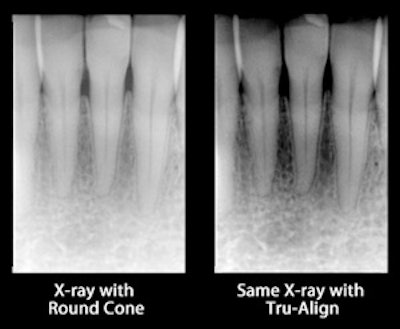

Tru-Align improves image quality by ensuring proper alignment, according to its developers. Left, an image taken using a round collimator; right, the same image taken with Tru-Align.